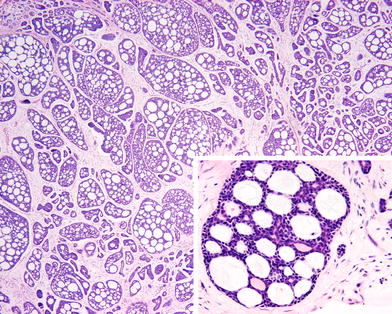

Fig. 5

Ceruminous adenoid cystic carcinoma. The overall cribriform (“Swiss-cheese”) pattern is seen on both the low power and within the inset